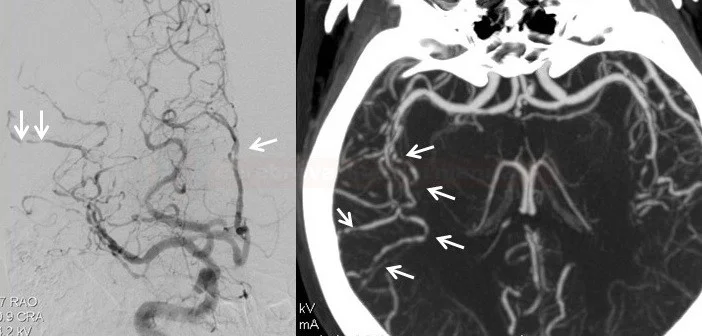

4. Αγγειογραφία εγκεφάλου (DSA / MRA / CTA)

• Αναζήτηση «beading» – εναλλαγές στενώσεων και διατάσεων σε πολλαπλά αγγεία.

• Πολλαπλές τμηματικές στενώσεις σε διάφορες αγγειακές περιοχές.

Η αγγειογραφία εγκεφάλου (ψηφιακή – DSA) είναι επεμβατική εξέταση. Χρησιμοποιείται για:

• αναζήτηση τυπικών στενώσεων/διατάσεων («beading»),

• αποκλεισμό άλλων αιτίων (ανευρύσματα, AVM, δυσπλασίες κ.λπ.).